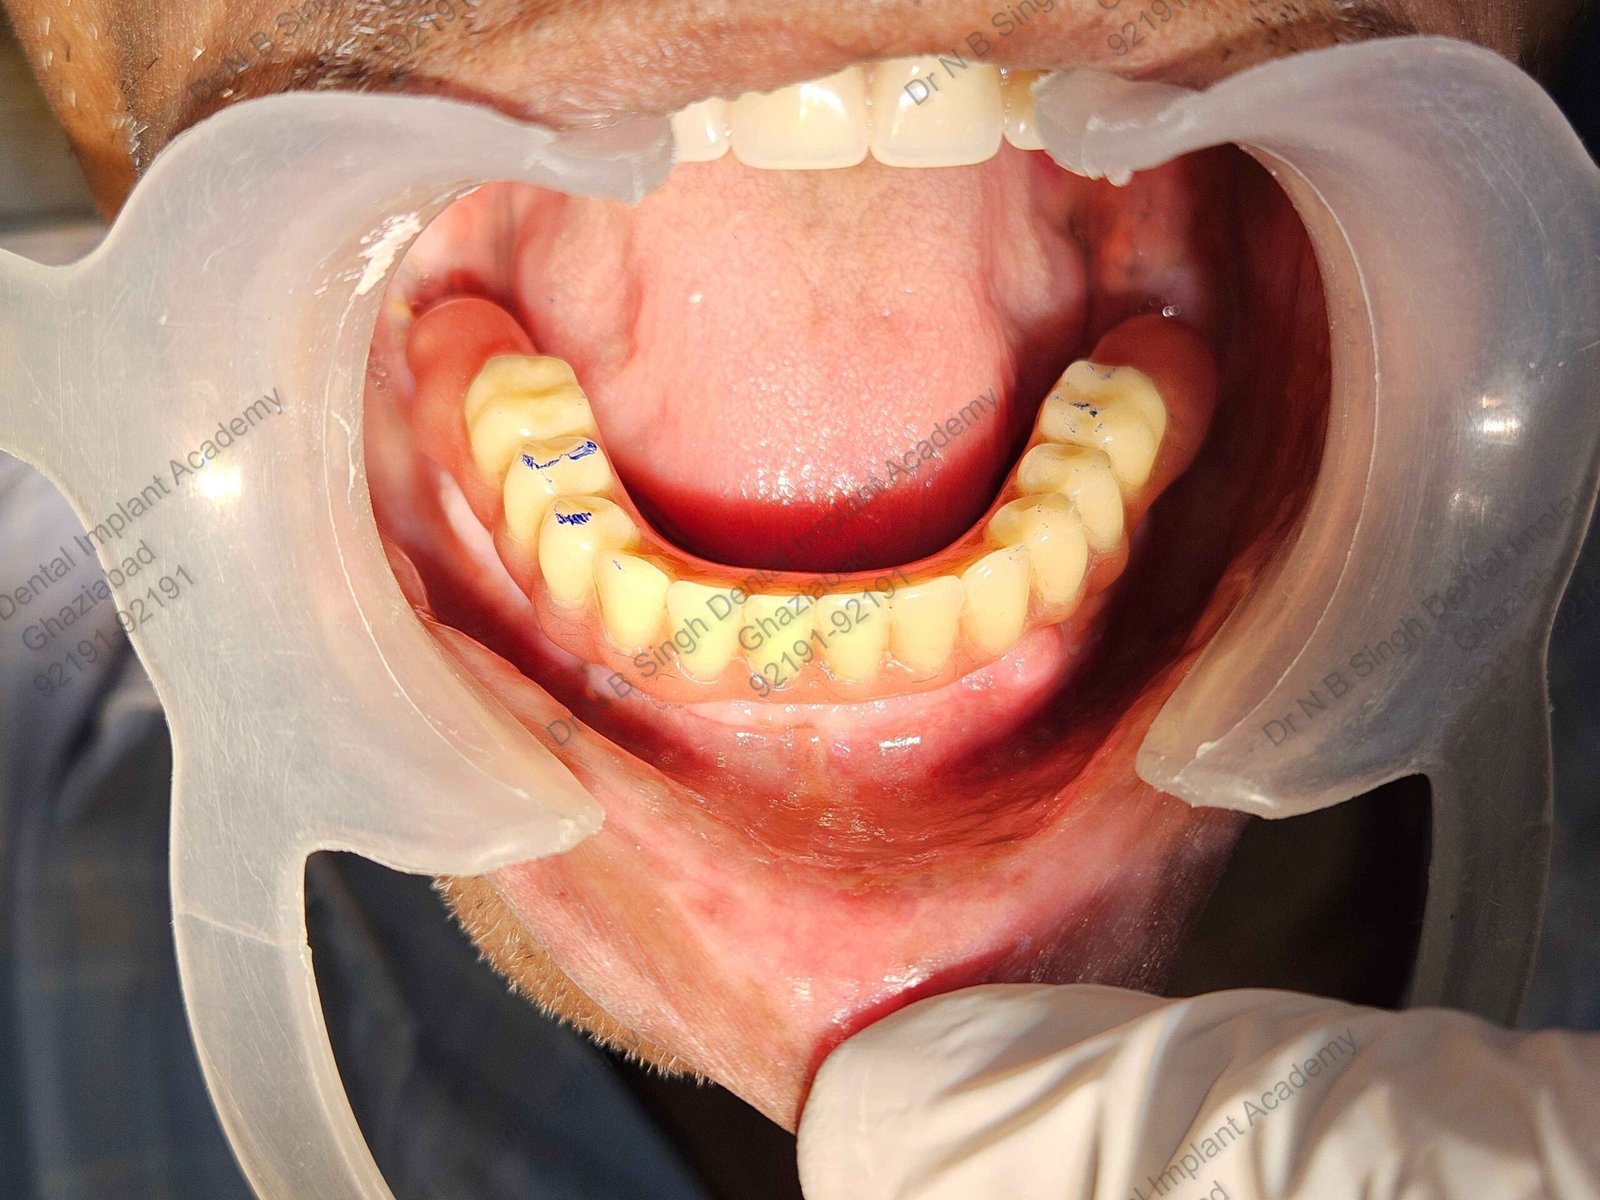

C1005 zygomatic basal implant full mouth – Ali Hasan 4